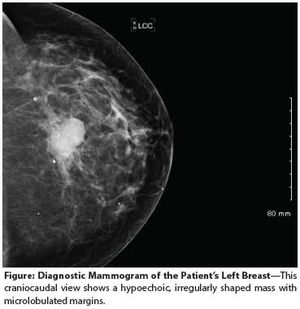

A 55-year-old perimenopausal woman presented with a palpable lump in her left breast. Diagnostic mammogram showed a 1.8-cm spiculated mass with scattered microcalcifications within the mass. Comparison with her most recent prior mammogram (about 9 months earlier) showed this to be a new mass.